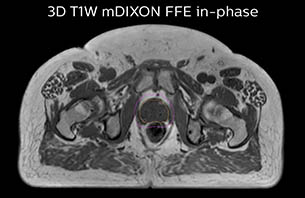

A 77-year-old male with prostate cancer cT3aN0M0, Gleason 8 and PSA 52 μg/L referred to androgen deprivation and radiation therapy with a prescribed dose of 50 Gy to the pelvic lymph node regions and 76 Gy to the prostate.

MR-only simulation workflow The 3D T1W FFE mDIXON sequence provides in-phase, water and fat images in one acquisition. Target and organs-at-risk are delineated on the 3D T2W TSE images. Prostate GTV is shown in orange, PTV in purple. The 3D bFFE sequence is used by the planner to mark the position of the fiducial markers (gold anchors) and contours are transferred to the digitally reconstructed radiographs (DRRs).

Based on the 3D T1W mDIXON images, MR-based density maps (MRCAT) are automatically generated. The VMAT (Volumetric Modulated Arc Therapy) plan is generated in TPS, based on MRCAT as primary image set. During the commissioning phase, dosimetric agreement between MRCAT-based and CT-based dose plans was studied and differences in the PTV dose were found to be minimal (<1% for most patients). Average difference in PTV mean values was 0.8% over the study group (n=62).